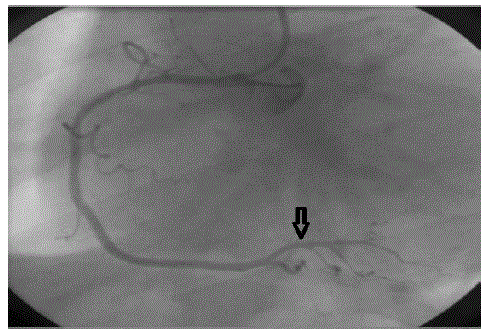

Qual o nome da estrutura anatômica indicada na seguinte imagem do cateterismo cardíaco?